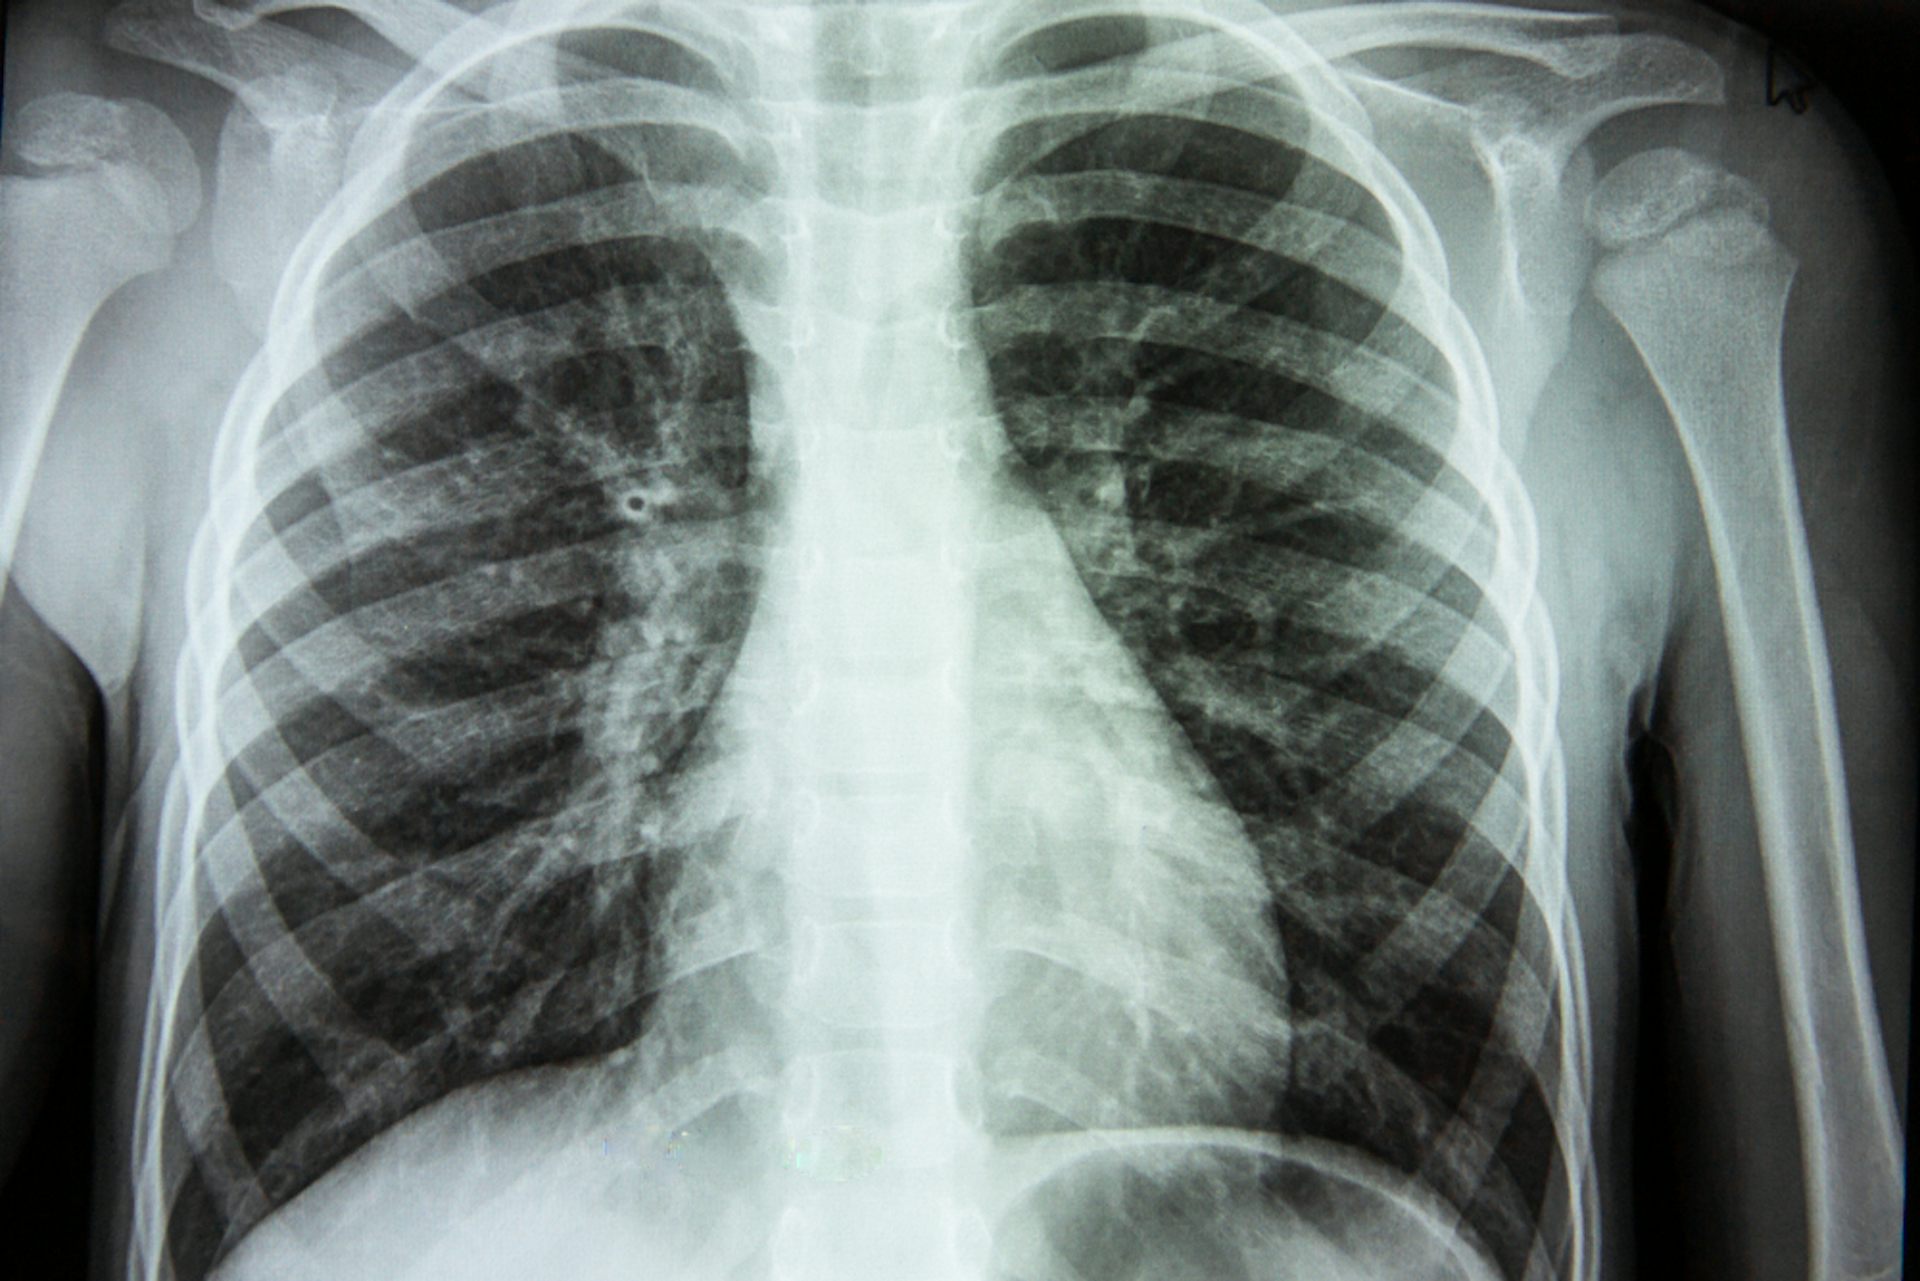

Chest-imaging techniques – such as computed tomography (CT) or X-ray – can be analysed by radiologists to search for visual markers of a COVID infection. Investigations early on in the pandemic found that abnormalities showed up in the chest radiography images of patients with the virus, leading the World Health Organization to recommend using radiography for diagnosing COVID when PCR testing isn’t available, especially for severe patients.

But there’s a resource bottleneck here, too. Using X-rays and CT scans for diagnosis requires radiologists to carefully decipher the chest images, since COVID’s visual pointers can be hard to spot. So, we created an artificial intelligence program to do this instead, to speed up diagnosis and allow radiologists to get on with their jobs.

We began by training and testing a number of different algorithms – some already existing, some that we had created – using a database of around 3,000 chest X-rays. These were a mix of scans from patients with COVID, healthy individuals and people with viral pneumonia. As we worked, we tweaked the algorithms to make them better at spotting the differences between the X-rays. Over time, we found that one clearly performed better than the others.

We then evaluated this top performer by giving it a completely new set of X-rays that it hadn’t seen before, and asked it to determine whether each came from a COVID patient or not. The program got the answer right 98.04% of the time.